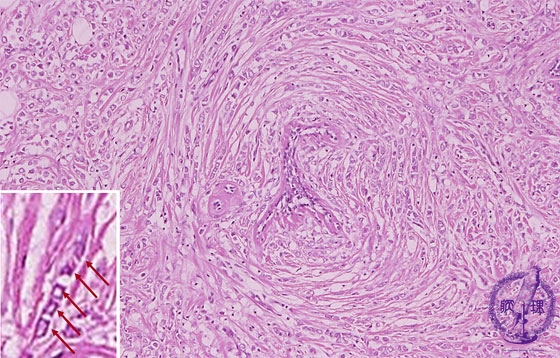

Microscopic image(HE stain, high power view):Stromal invasion of lobular carcinoma. Relatively small carcinoma cells with high N/C ratio infiltrated to the stromain a so-called “Indian-file”manner(inset, arrow).This finding is characteristic of invasive lobular carcinoma.